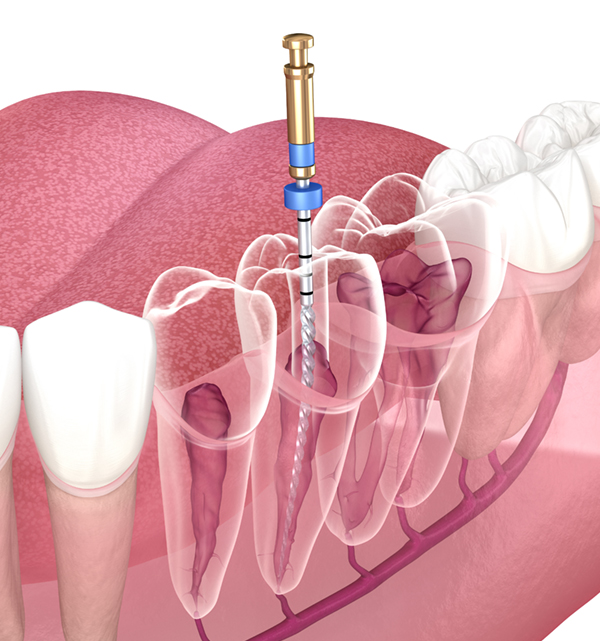

Perawatan gigi lengkap, aman, dan nyaman dengan dokter profesional. Mulai dari pasang behel hingga bleaching gigi dengan teknologi modern.